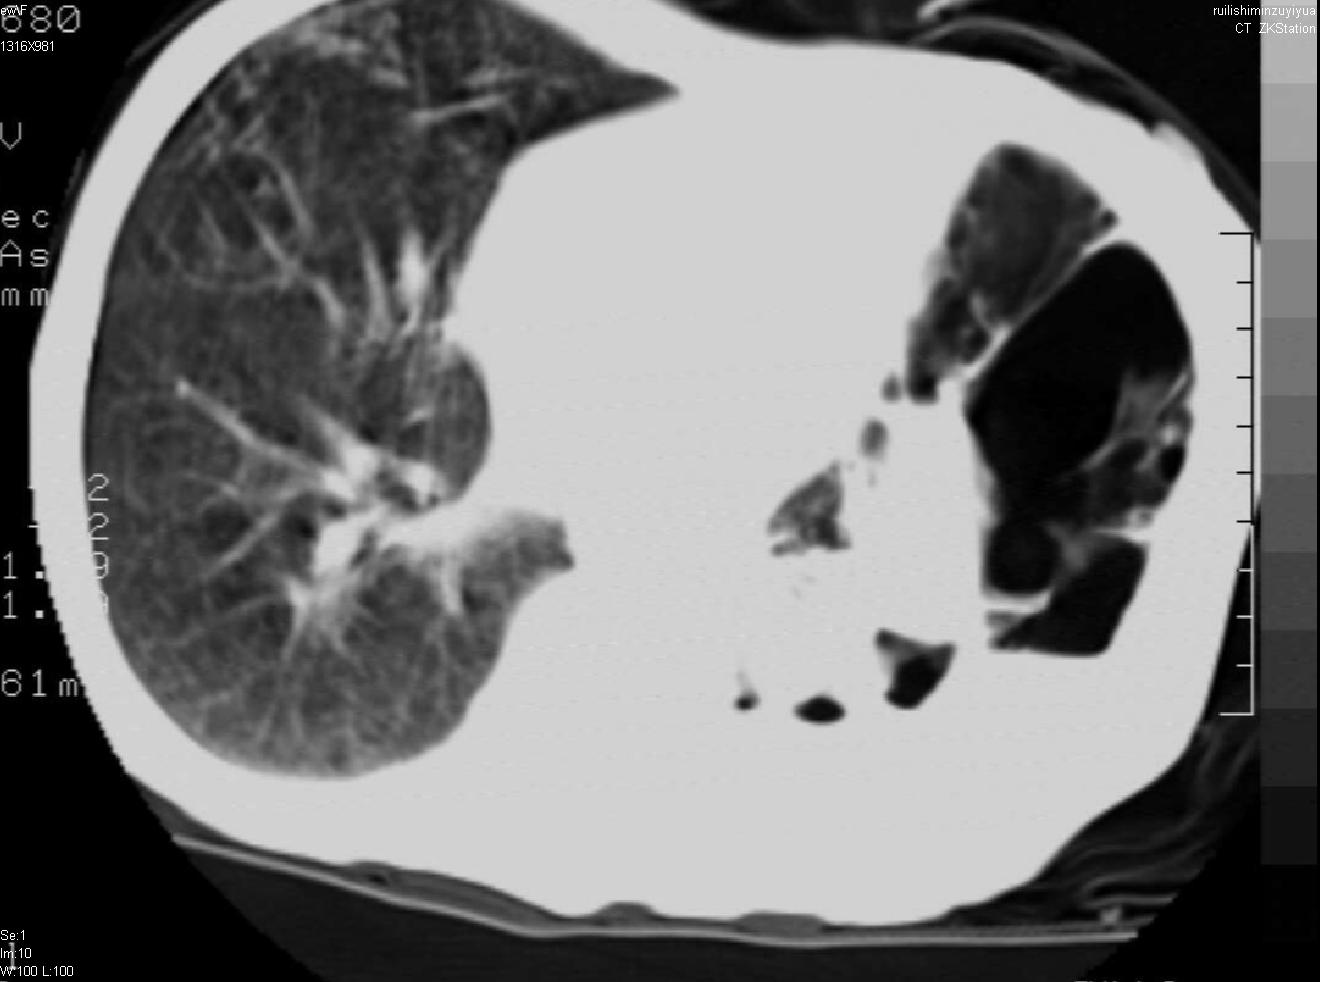

以下是引用天南地北在2007-6-11 23:32:00的发言:[br]1:左侧肺毁损(结核性)伴感染(多发空洞伴液平面)。[br]2:右肺继发型肺结核。

以下是引用avril在2007-6-12 1:17:00的发言:[br]1、左肺毁损。[br]2、左肺多发肺大泡伴自发性气液胸形成。[br]3、右肺继发型结核。